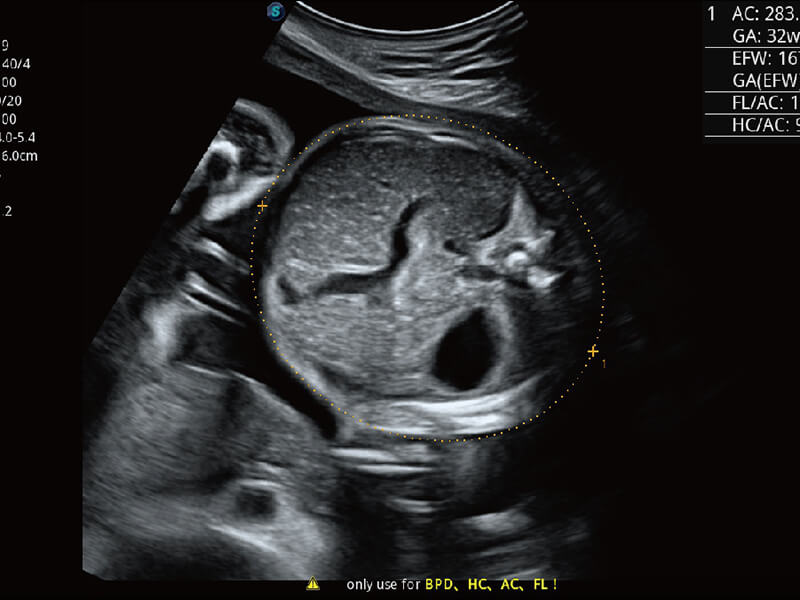

S60探头工艺,从前端信号处理每一个环节采集无损声学数据,真实还原组织原貌,再现解剖细节。